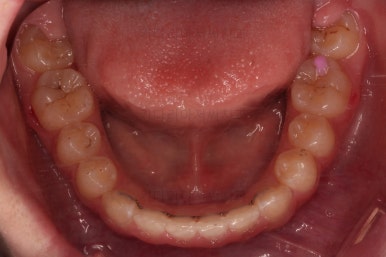

초진 시 입안의 모습입니다.

앞니가 안으로 굽어 들어간 양상인데요. 흔히 "옥니"라고 표현합니다.(뻐드렁니의 반대개념)

전반적으로 치열이 삐뚤삐뚤하고요.